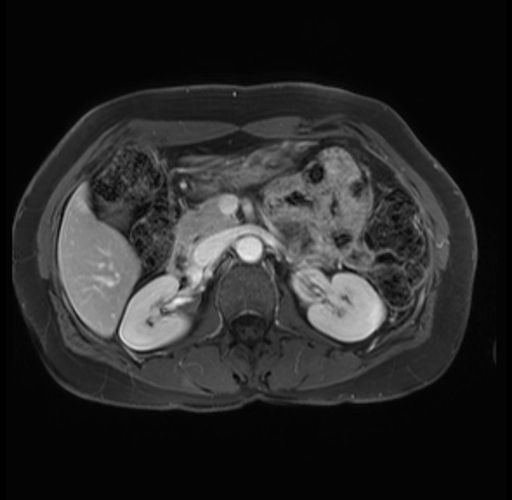

Imaging Analysis

Look through the patient's CT scan to identify any areas of concern for the necessary procedure.

Based on your CT findings, which issue(s) are present and would give reason for "planned slowing down moment(s)" in this case?